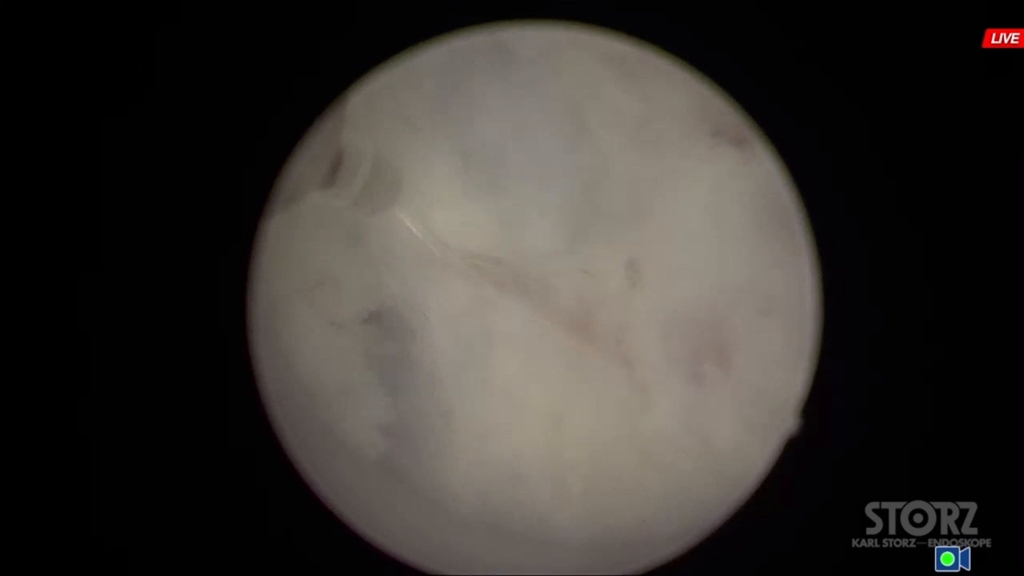

Трансуретральная энуклеация простаты (dornier medilas solvo h35)

08 апр 2022

ДГПЖ